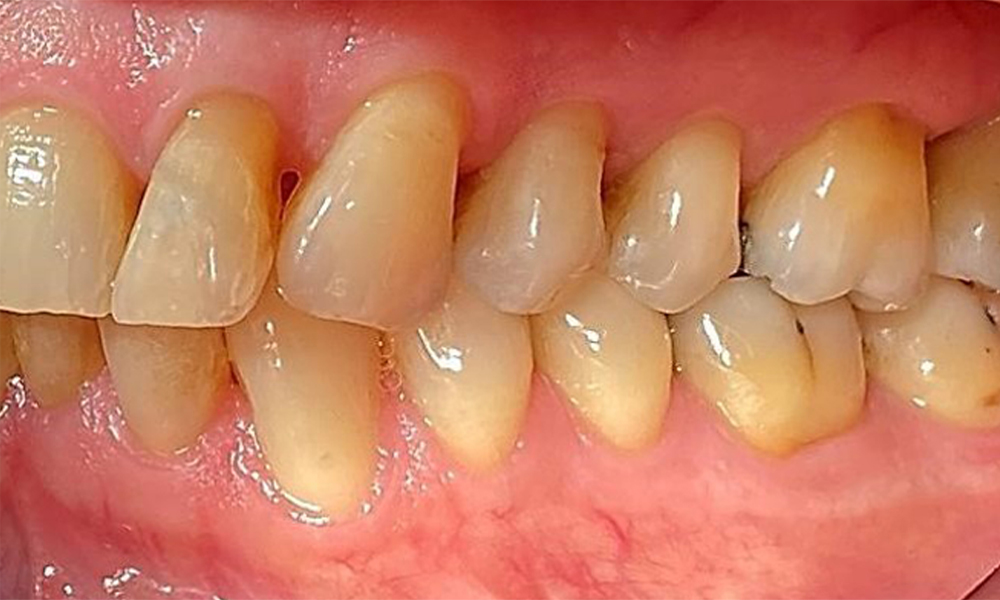

Left lateral view including the recessions.

Fig. 4 Left lateral view including the recessions. © Dr R. Krapf

The patient has stage II, grade B periodontitis (5). At 1 to 3 mm, the clinical probing depths were within the physiological range. Localized probing depths of 5 mm were observed on the mesiopalatal aspects on both 17 and 27. There are generalized recessions of 1–3 mm with partial loss of the interdental papillae (Fig. 2, Fig. 3, Fig. 4)